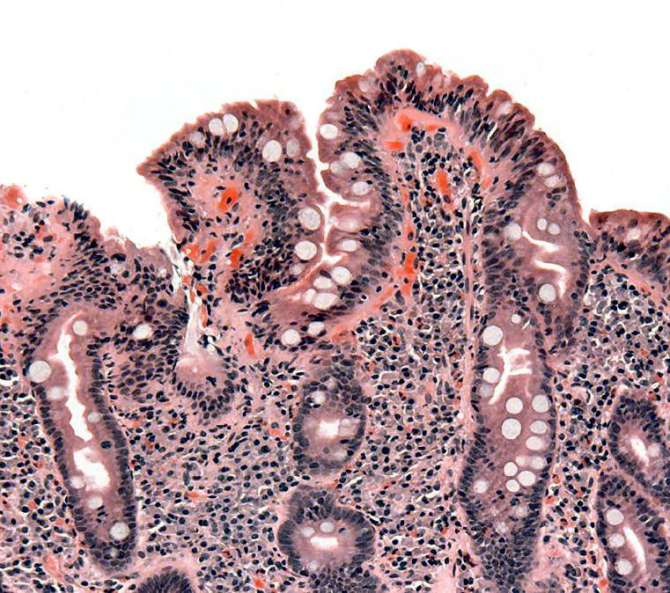

-Enfermedad celíaca: reacción inmunitaria al gluten que daña el intestino delgado.

![[Img #76953]](https://noticiasdelaciencia.com/upload/images/10_2025/8021_coeliac_path.jpg)

(Foto: Wikimedia Commons)